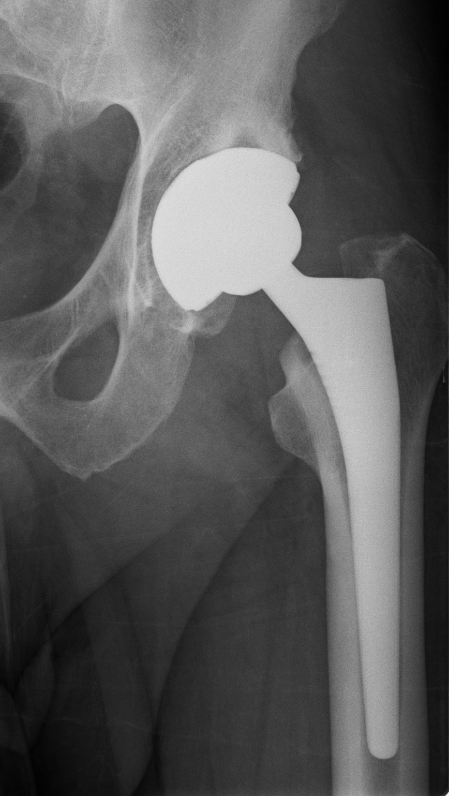

Below you see X-ray examples of patients with severe osteoarthritis of the hip before (Fig 1) and after (Fig 2) total hip replacement, and of the knee before (Fig 3) and after (Fig 4) total knee replacement that have been successfully treated under Mr Weitzel’s care.